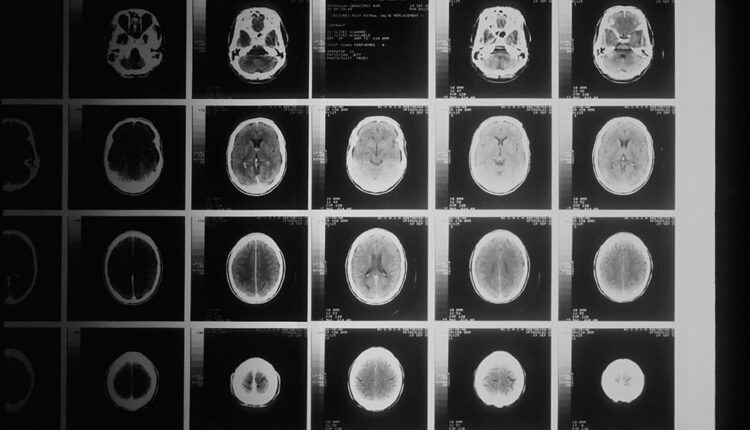

ہانگ کانگ: محققین کی ٹیم نے ایک ایسا اے آئی ماڈل تیار کیا ہے جو نوعمروں میں نفسیاتی عوارض کا پتہ لگانے کے لیے دماغی اسکینز کا تجزیہ کر سکتا ہے۔

میڈیا رپورٹس کے مطابق ہانگ کانگ سے تعلق رکھنے والی ریسرچ ٹیم نے ایسا اے آئی ماڈل تیار کیا ہے جو دماغی اسکینز کا تجزیہ کرکے نوعمروں میں ذہنی عارضوں جیسے ڈپریشن، پریشانی، اے ڈی ایچ ڈی، موڈ کی خرابیوں اور سائیکوسس کا پتہ لگا سکتا ہے۔